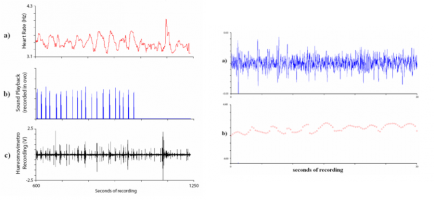

Rationale: Cystic fibrosis (CF), is a disease characterized by airway liquid surface dysregulation, decreased depth of

En el ámbito de la investigación con huevos aviares, resulta útil la observación del pulso cardiaco y los movimientos del embrión dentro del huevo durante su incubación, ya sean parte de su desarrollo o respuesta a estímulos sensoriales. El sistema presentado es un balistocardiógrafo de alta sensibilidad y bajo coste, implementado mediante cápsulas fonográficas. El sistema permite monitorizar de forma constante y no invasiva la señal correspondiente al pulso cardiaco y los movimientos del embrión dentro del huevo en desarrollo.